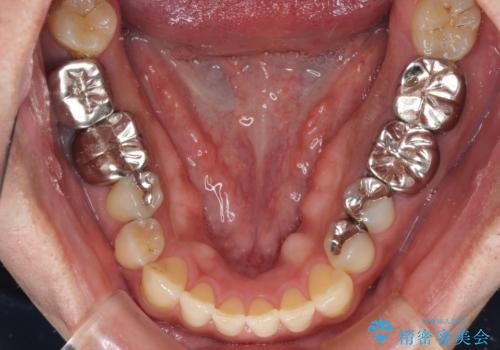

前歯の反対咬合が改善する過程では、奥歯が咬みにくくなるため、食事では辛い思いをされていたようです。

矯正治療後は安定した咬み合わせとなり、顎の違和感がなくなったとのことでした。

今後はむし歯や銀歯を治療していく予定です。